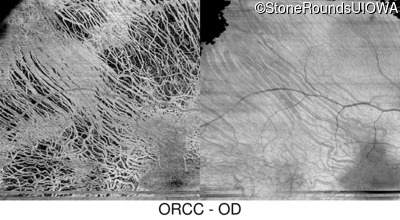

Infrared Fundus Photograph - Right - 20/16

Exemplar

Infrared Fundus Photograph - Left - 20/12.5 -2